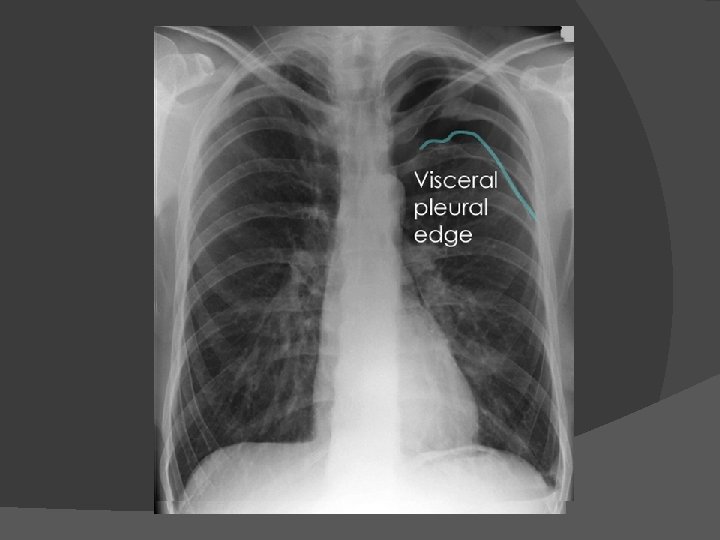

Pneumothorax